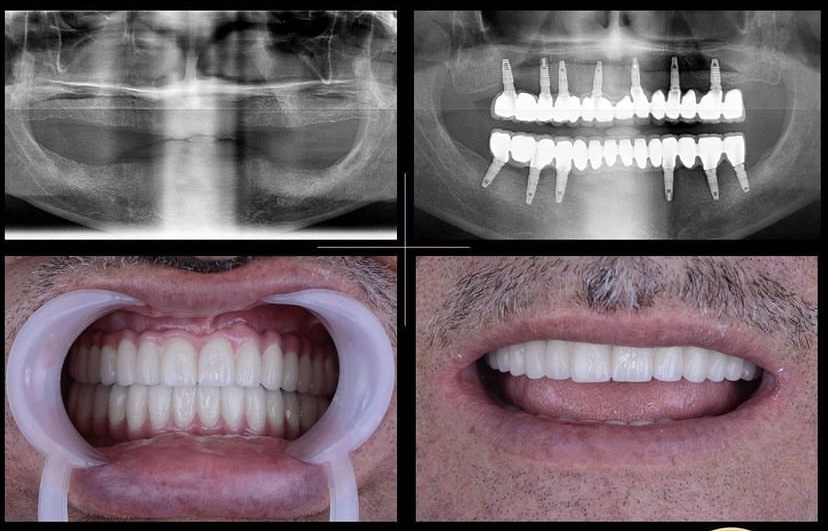

Öncesi̇-Sonrası Resi̇mler

Galeri Öncesi̇-Sonrası Resi̇mler